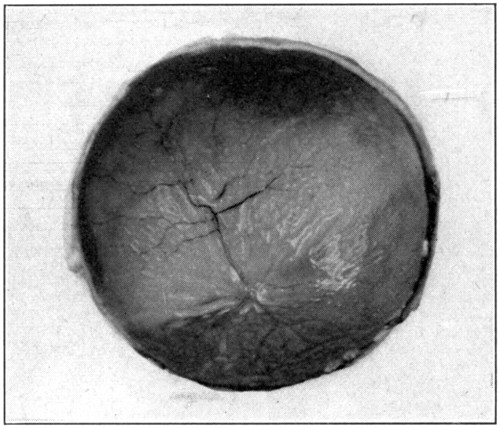

The posterior half is taken first because it is the simplest and easiest of the two halves to dissect. In this half of the eye the retina may be readily seen through the vitreous; the choroid and its apparent iridescent colors through both vitreous and retina. (Fig. 10.)[41] Remove the vitreous by simply tilting this half of the eye, and with the finger push out the vitreous.

Fig. 10—The retina, retinal vessels, and iridescent choroid showing through the vitreous.

Whichever method for removing the vitreous is followed, the retina will be left rather badly wrinkled and out of place. If the last-mentioned method, which is really the best of the[42] three described, is the one adopted, the retina will be left in an entirely collapsed and folded form. In any case, to straighten out the retina against the choroid, immerse the whole posterior half in water, inside uppermost. The retina will then slowly unfold itself and lie flat against the choroid. With the tweezers remove[43] the whole half from the water; tilting it slowly to empty it of all the water, and, having done so, turn it down upon the table rather forcibly in order to help it drain itself of all the water.

Notice the thinness of the retina, and, also, that the seeming iridescence of the choroid shows through. The optic disc, which is the point of entrance of the optic nerve, and the optic cup are easily recognized, though neither will be seen as large as when viewed in the living eye with an ophthalmoscope. The blood vessels of the retina, as they ramify outward or forward, after their entrance through the optic nerve through which they pass, are also very plainly seen. A closer inspection will show, in the very centre of the “entrance” of the optic nerve, a whitish, pointed vessel, about 1 or 2 mm. long. That is the sloughed-off and atrophied end of the hyaloid artery, which, when the eye was in an embryonic state, ran forward from the central artery of the retina through the hyaloid canal to the posterior surface of the[44] lens. With the forceps pick up the peripheral edge of the retina, and, by pulling gently upward, tear it away from its apparent place of attachment to the “entrance” of the optic nerve. (Fig. 12.) When this has been done, there will be seen some threads protruding[45] from the optic nerve. Filling the half with water will tend to separate these strands, which are optic-nerve elements.

Fig. 12—Picking up the retina in order to tear it away from the entrance of the optic nerve.

Fig. 13—The lighter area is the field of iridescence of the choroid.

After the removal of the retina, the iridescence of the choroid (tapetum lucidum) (Fig. 13) may be examined with a hand lens, or, after its removal, a piece may be cut and placed under a microscope. This iridescence is, of course, not present in the human[46] eye. (“Physiology of the Senses,” McKendrick & Snodgrass, page 101.)